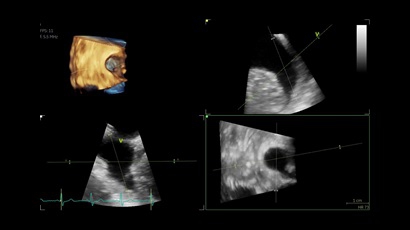

• Vivid IQ 4D с поддержкой технологии объемной реконструкции

• Передовые технологии, такие как 4D чреспищеводная эхокардиография, ЭКГ, стресс-эхо, внутрисердечная ультразвуковая эхокардиография, тканевый доплер и другие.

4D:

Да

• Режимы: 4D, 2D (B-режим), цветной допплеровский режим, режим энергетического допплера, M-режим, цветной M-режим, спектральные режимы импульсно-волнового допплера (PW) и непрерывно-волнового допплера (CW), визуализация скорости движения тканей.

• 6VT (биплан/триплан).

• 4D AUTO AVQ - модуль автоматического выравнивания, сегментации и обсчета размеров кольца аортального клапана по объемным данным.

• 4D AUTO LVQ - модуль расчета массы миокарда ЛЖ на основе данных 4D-исследования.